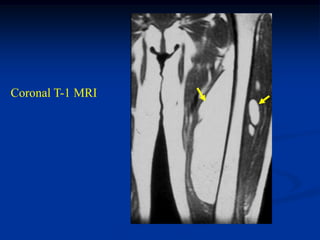

CLASSIC     Case #285         Sagittal T-1 MRI

67 year female with myxoid liposarcoma knee

Sagittal T-2 MRI

Axial T-2 MRI